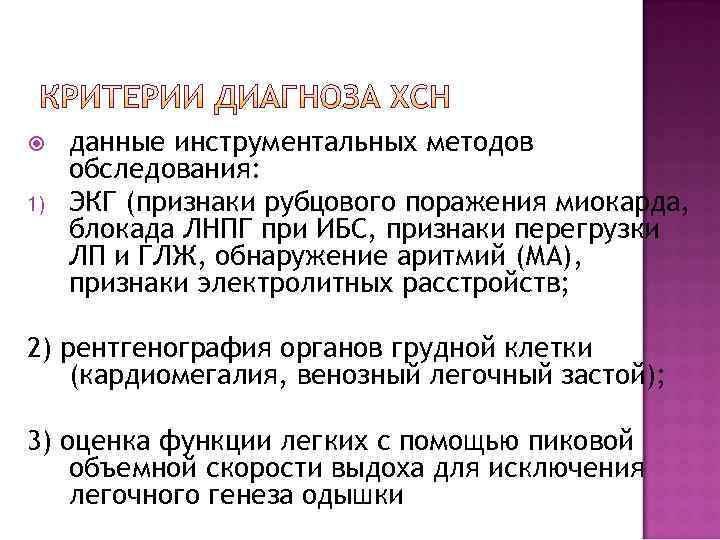

1) данные инструментальных методов обследования: ЭКГ (признаки рубцового поражения миокарда, блокада ЛНПГ при ИБС, признаки перегрузки ЛП и ГЛЖ, обнаружение аритмий (МА), признаки электролитных расстройств; 2) рентгенография органов грудной клетки (кардиомегалия, венозный легочный застой); 3) оценка функции легких с помощью пиковой объемной скорости выдоха для исключения легочного генеза одышки

1) данные инструментальных методов обследования: ЭКГ (признаки рубцового поражения миокарда, блокада ЛНПГ при ИБС, признаки перегрузки ЛП и ГЛЖ, обнаружение аритмий (МА), признаки электролитных расстройств; 2) рентгенография органов грудной клетки (кардиомегалия, венозный легочный застой); 3) оценка функции легких с помощью пиковой объемной скорости выдоха для исключения легочного генеза одышки